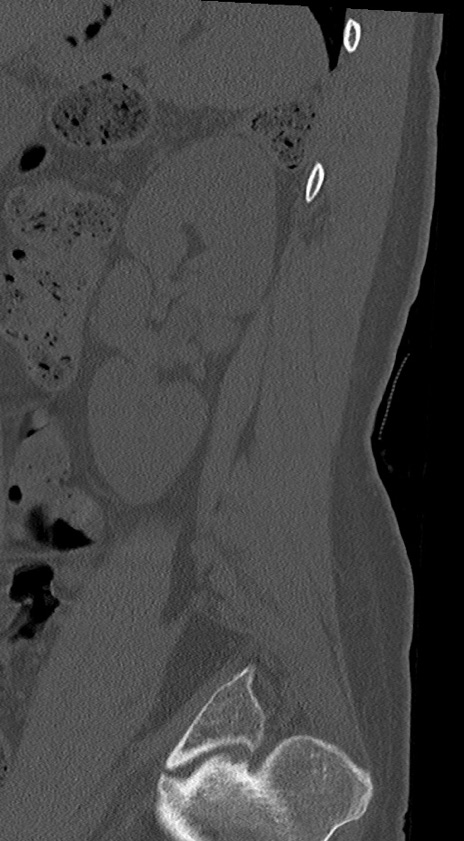

【整形】TIPS症例4 腰椎CT(矢状断像)

腰椎CT

冠状断像